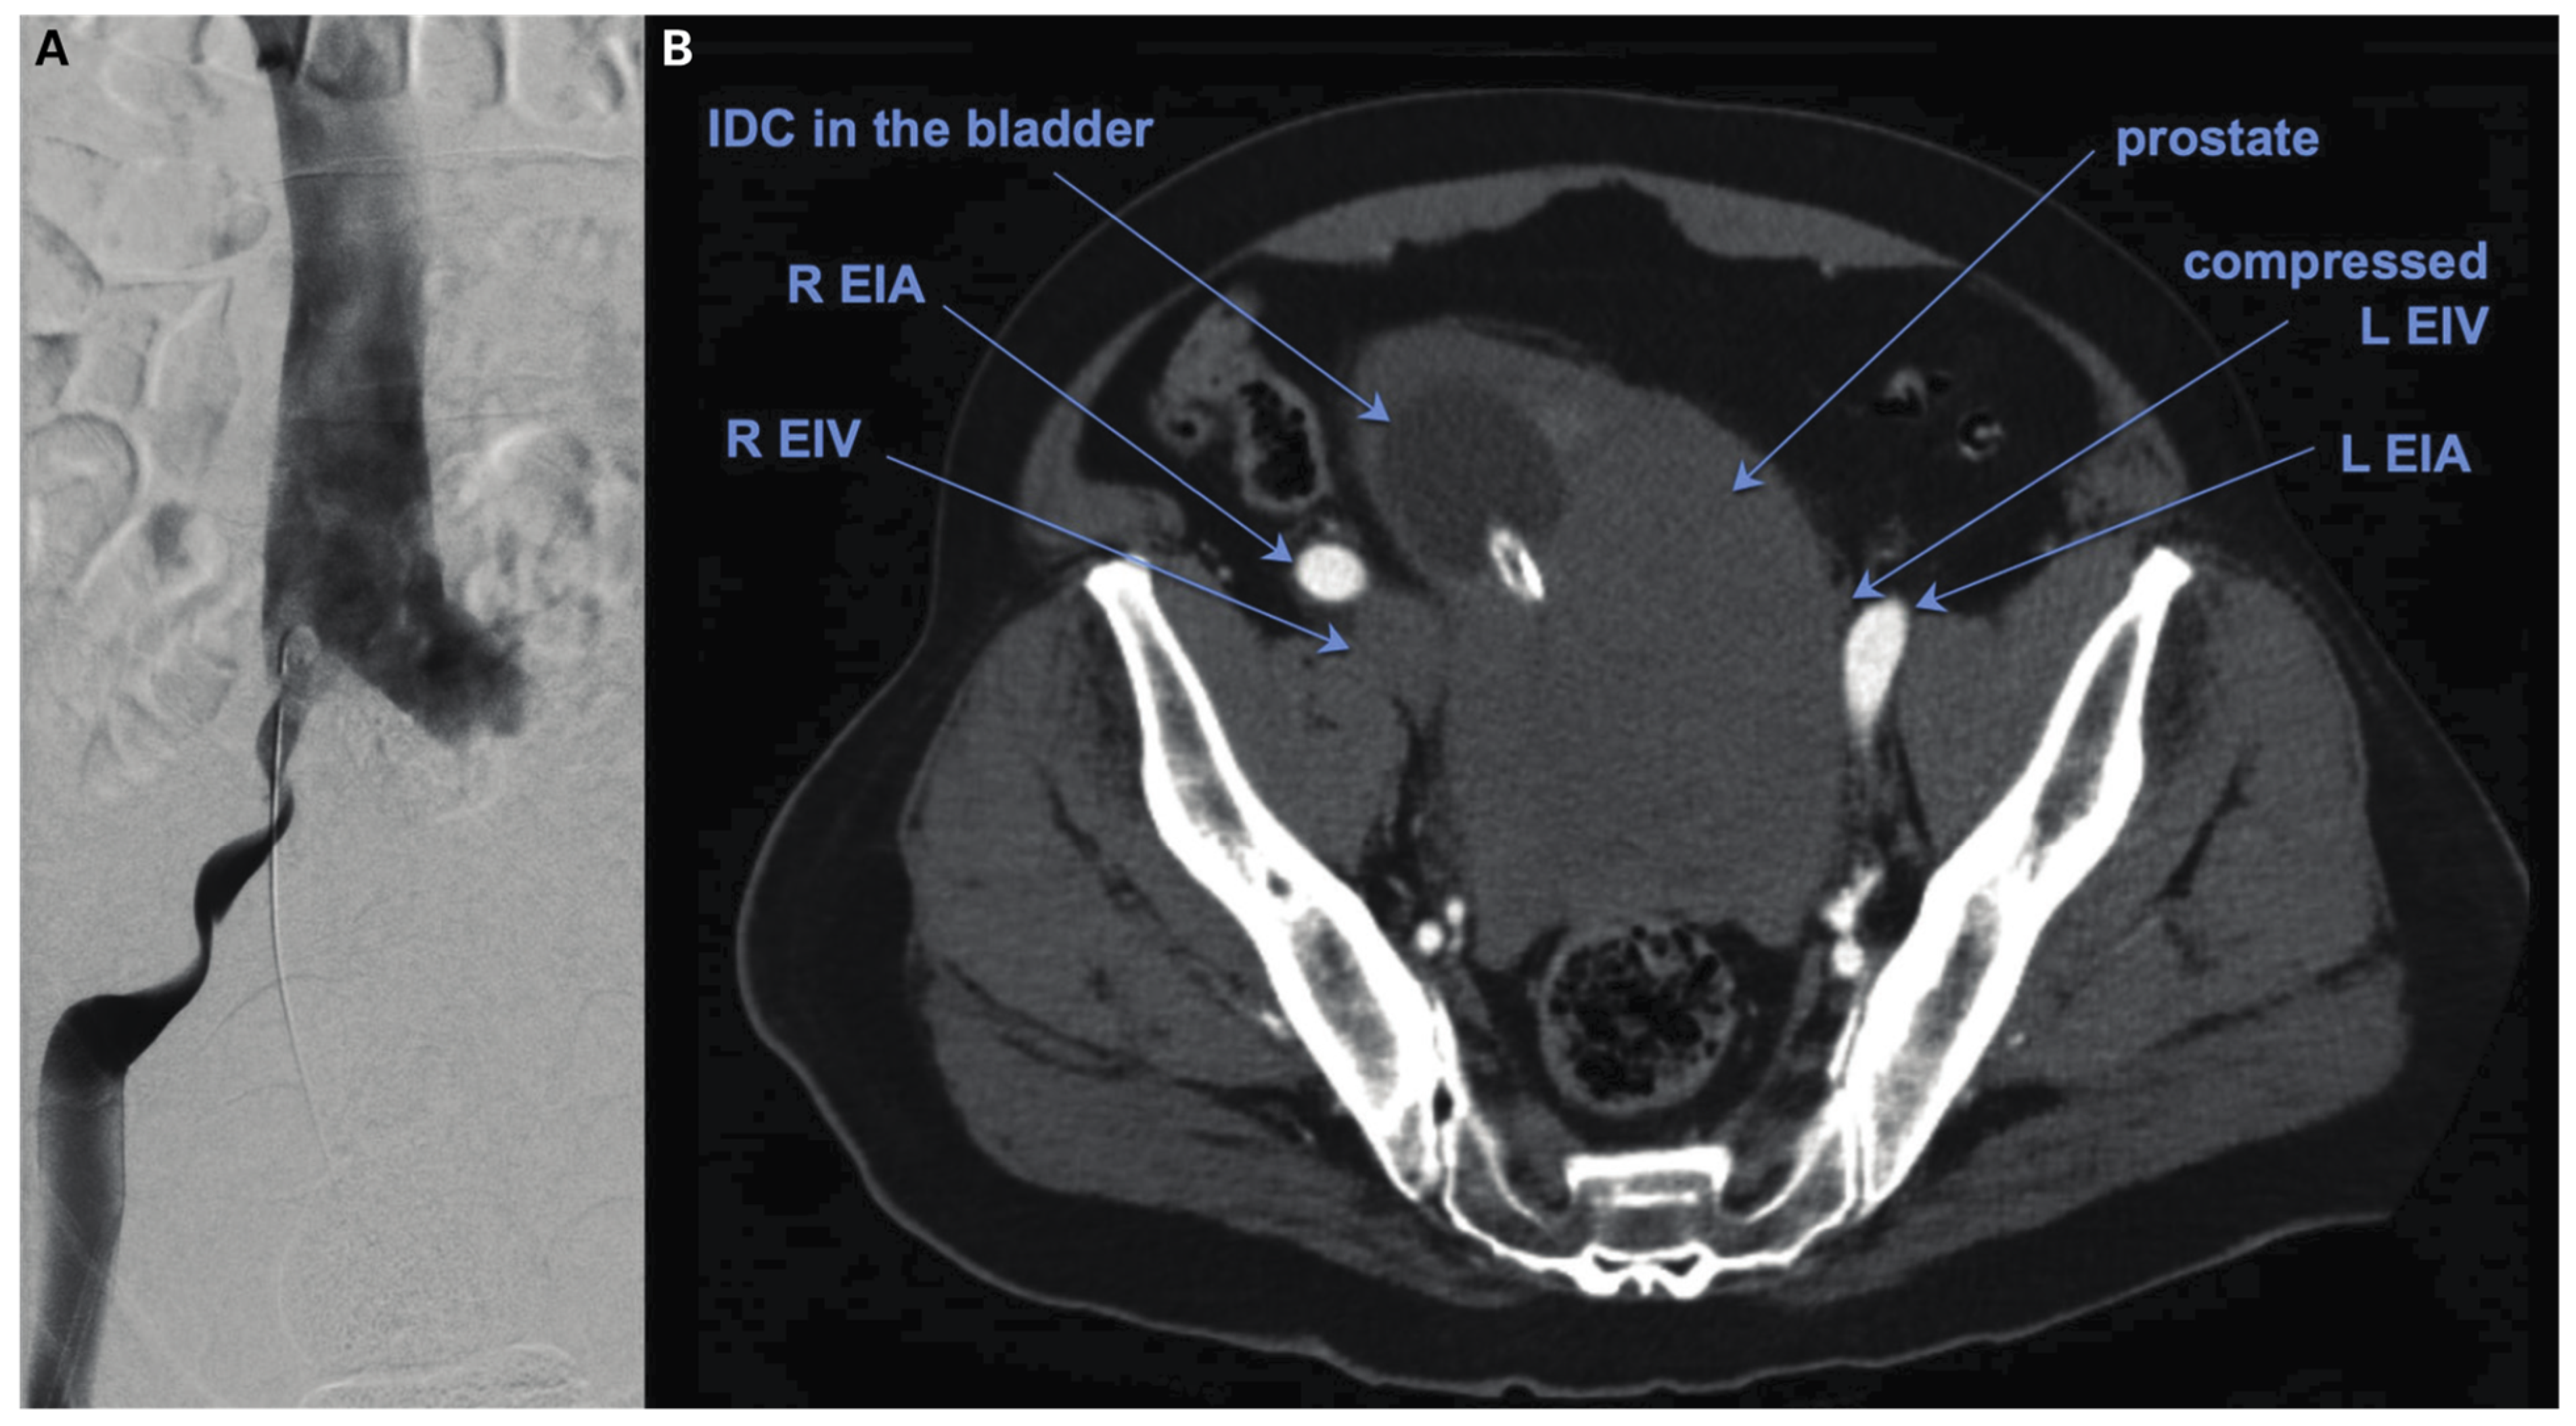

Prostate Artery Embolisation of Megaprostate Causing External Iliac Vein Compression